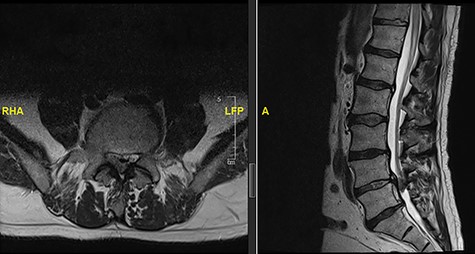

The updated MRI scan showed large disc prolapse at L4/5 level (Fig. 4) and the patient underwent emergency laminectomy/discectomy at L4/5. Post-operatively the patient’s pain improved however there still a retained loss of perineal sensation to pin-prick, a urinary catheter tug awareness was present and a good lower limb power was documented. The patient was discharged on the third post-operative day having been successfully mobilized and decatheterized with spontanous micturition.

The patient represented just over a month following the surgery to report about new onset weakness in the plantar flexion bilaterally, urinary incontinence, persistence of perineal sensation loss and new erection problems. There was no report of any pain and ambulation was still at ease. An MRI scan was organized a few days later (Fig. 5). The finding was deemed to be an IDH. Therefore, revision surgery followed the next day, with a durotomy and extraction of intradural disc fragments. As the patient had sphincter disturbance with neurogenic bladder and bowel difficulties, a referral to the regional spinal injury unit for aftercare as well as to the sexual dysfunction clinic for erection problems were organised.